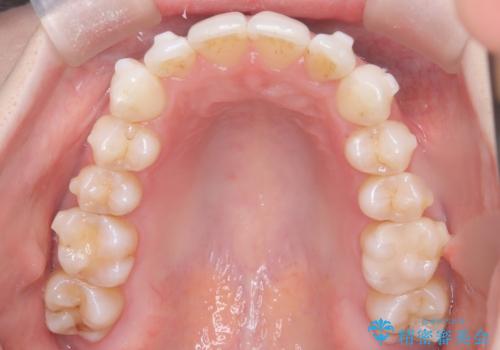

矯正後の後戻りで前歯にガタツキができてしまった インビザラインで改善

- 子どものときにワイヤー矯正をしていたが、後戻りによって前歯のガタツキが気になってきたとのことで来院されました。

アライナー矯正希望だったため、インビザラインによる治療を行いました。

前歯のガタツキを改善する治療法として、マウスピース矯正が適していることが多いです。

マウスピース矯正は、金属製のブラケットやワイヤーを使用せずに、透明なマウスピースを装着して歯を移動させる方法です。そのため、目立たず、痛みも少ないです。